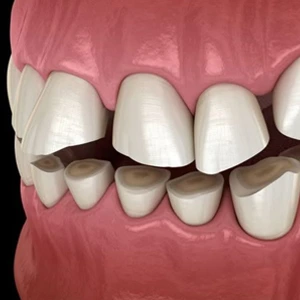

Bite Misalignment

Feeling that teeth don't meet correctly (malocclusion), or that bite suddenly feels different — often a direct indicator of disc displacement.